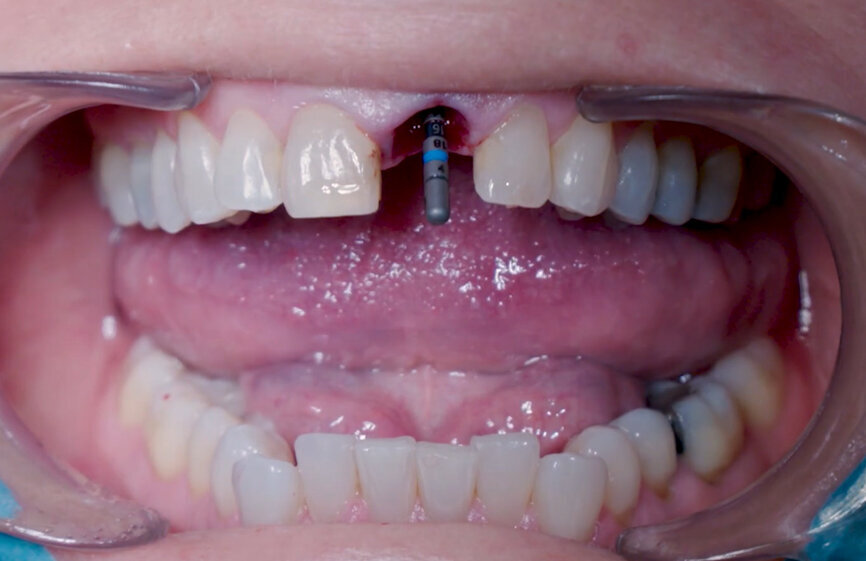

Fig. 10: Implant placement with surgical handle.

Intra-sulcular incisions were performed to release the marginal gingival fibres to allow a minimally invasive extraction. The socket was carefully cleaned to remove any ligament and debris left. Special attention was given to assessing the alveolar wall integrity. A distance of 3 mm was observed between the gingival margin and the labial wall margin. Implant bed preparation considered a medium-density bone workflow, starting with the needle drill aimed at the palatal wall to create an entry point for the next drills, creating an osteotomy that allows for a greater area of implant engagement (Fig. 5). The Ø 2.2 mm pilot drill was used to the respective implant length planned, followed by the use of an alignment pin to check the 3D orientation (Figs. 6 & 7). The Ø 2.8 mm and Ø 3.2 mm drills were used to finalise the osteotomy (Fig. 8). The site was then properly probed to assess for possible wall perforation. A 4 × 14 mm implant was placed, starting with the surgical handle engaging the apical part of the implant, following the same orientation as that of the needle drill and correcting the implant direction as it moved within the osteotomy (Figs. 9 & 10). Primary stability (45 Ncm) was achieved at the final position. After placement, the implant position was verified horizontally with an occlusal mirror and vertically with a surgical probe, and at this point, the abutment gingival height was selected (Figs. 11 & 12). A healing abutment was placed on to the implant (Fig. 13) to protect the connection so that granular bone substitute (Straumann XenoFlex) could be applied in the gap between the implant and labial wall. This was gently compacted in with the 2.8 mm side of the surgical probe (Figs. 14–16). Collacone (botiss biomaterials) was used to keep the bone granules away from the gingival margins in order to avoid softtissue fenestration and fibroblastic infiltration (Figs. 17 & 18).

Prosthetic procedure

A Ø 4 mm temporary abutment with a gingival height of 2.5 mm was placed on to the implant, and it showed no crestal bone interference, allowing for appropriate creation of the emergence profile (Fig. 19). The tooth shell, which was designed and milled in PMMA prior to the procedure (Figs. 20 & 21), was tested to ensure that the contours and retention wings were appropriate and caused no interference (Figs. 22 & 23). The palatal side, including a small portion of the incisal edge, was opened in order to allow screw channel access (Figs. 24 & 25). The lateral wings of the tooth shell allow the provisional temporary crown to stay immobile during the pick-up procedure, which is a common problem clinicians face when performing the immediate pick-up technique. The tooth shell was bonded to the temporary abutment using flowable light-polymerising composite, and a slim emergence profile was created to the subgingival portion using the same material (Fig. 26). At this point, the retention wings were removed. With no compression to the soft tissue, the provisional crown was seated and the incisal edge adjusted to ensure that the antagonist tooth was not touching it in excursive movements. The provisional crown was torqued to 25 Ncm, and the screw access hole properly closed and polished (Fig. 27). The patient was seen seven days later for postoperative and periapical radiographic control (Figs. 28 & 29).